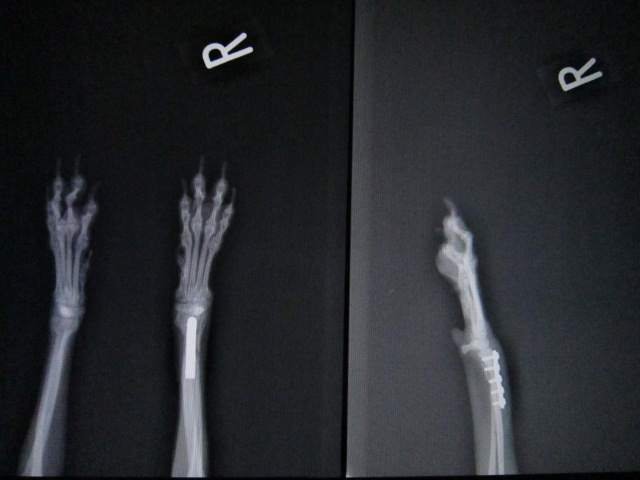

パピヨン ♀ 8か月 2.1kg

さくを飛び越えたときにキャンと鳴いて右前足を痛がっているとのことで来院。レントゲンにより、右橈尺骨遠位端骨折を確認した。

1週間外固定で様子を見たが悪化したため、手術によりプレート固定を行った。

術前のレントゲンです。

右前肢橈尺骨遠位端骨折です。